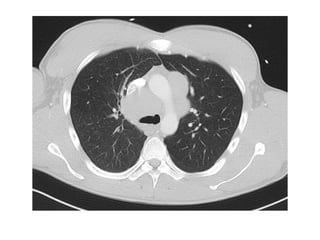

2-Interstitial Fibrosis (Asbestosis) :

-Asbestosis refers exclusively to asbestos-related interstitial

pulmonary fibrosis

-The changes of asbestosis are more pronounced in the

lower lobes and subpleurally but often extend to involve

the middle lobe and lingula, upper lobes can be involved

in advanced cases

-Honeycombing, as in other fibrotic lung diseases, can

occur in advanced disease

-Features on chest radiographs include ground-glass

opacification, small nodular opacities, “shaggy” cardiac

silhouette, and ill-defined diaphragmatic contours, it has

been reported that 80% of patients with asbestosis have

coexistent pleural disease at chest radiography, fibrous

bands are sometimes seen to radiate inward from the

pleura

-HRCT :

*An early feature is a subpleural curvilinear opacity, this

finding represents peribronchiolar fibrosis

*Parenchymal band-shaped opacities project in from the

pleura and represent fibrosis along bronchovascular

sheaths or interlobular septa

*Other features that have been reported include ground-

glass opacification (due to mild alveolar wall fibrosis

beyond the resolving power of CT, subpleural nodular or

dotlike opacities, thickening of interlobular septa, and

honeycombing